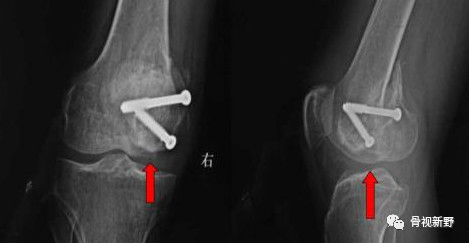

Buttress理念:由于Hoffa骨折垂直剪力较大,单纯拉力钉固定易致骨折移位、畸形愈合或不愈合。

因此,使用防滑、支撑的Buttress钢板以对抗垂直剪力有一定的必要性。